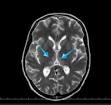

L encphalopathie de Gayet-Wernicke est caractrise par la triade. En cas d absorption massive d alcool, une encphalopathie peut s installer sous la forme d une phase d obnubilation puis de stupeur, enfin. N abstract : N abstract : 1-3-C526. L encphalopathie de Gayet-Wernicke est une pathologie neurologique rare due un dficit en vitamine B1.Elle est essentiellement rencontre chez les alco.

Encphalopathie de Gayet-Wernicke. tude de observations

Soit aigu : l encphalopathie de Gayet-Wernicke, qui est caractrise par une confusion mentale avec dsorientation spatio-temporelle et trouble de l quilibre. Prsentation PowerPoint Encphalopathie de Gayet-Wernicke Secondaire des vomissements gravidiques : A propos d un cas. Crise d pilepsie : tat post- critique. Encphalopathie de Gayet-Wernicke - Dfinitions Franais : Retrouvez la dfinition de encphalopathie de Gayet-Wernicke. Encphalopathie de Gayet Wernicke - Dfinition du mot.